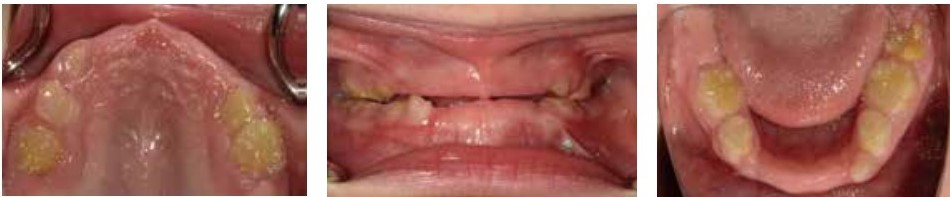

2015年になって、日本では世界に先駆けて根本治療薬が使われるようになり、人工的に作ったアルカリホスファターゼを補充することで、これまでは生存が困難であった重症なタイプの患者さんの命がつながる症例が増加してきました。私たちの診療室でも、そのような患者さんの受診が増えてきて、典型像とされてきた「歯根が長いまま脱落した乳歯」とは違う所見に多く遭遇しました。そこで考えたのが、全身の骨の形成がよくないほどの重症なタイプでは、歯全体の形成にも問題があり、歯根自体があまりできていなかったり、歯冠の形成がよくなかったりするということです(図2・3)。このことから、低ホスファターゼ症は、重症なタイプと軽症なタイプとを分けて考える必要があるのではないかという考えに至りました。

(図2)低ホスファターゼ症の一例(重症なタイプ:6歳4か月男児)

多数歯が脱落しており、残乳歯にも形成不全を認める。

(図3)低ホスファターゼ症の一例(重症なタイプ:図2と同一患者さん)

7歳0か月時のパノラマエックス線画像では、萌出歯の形成不全を認め、永久歯胚の形成状態もよくない。